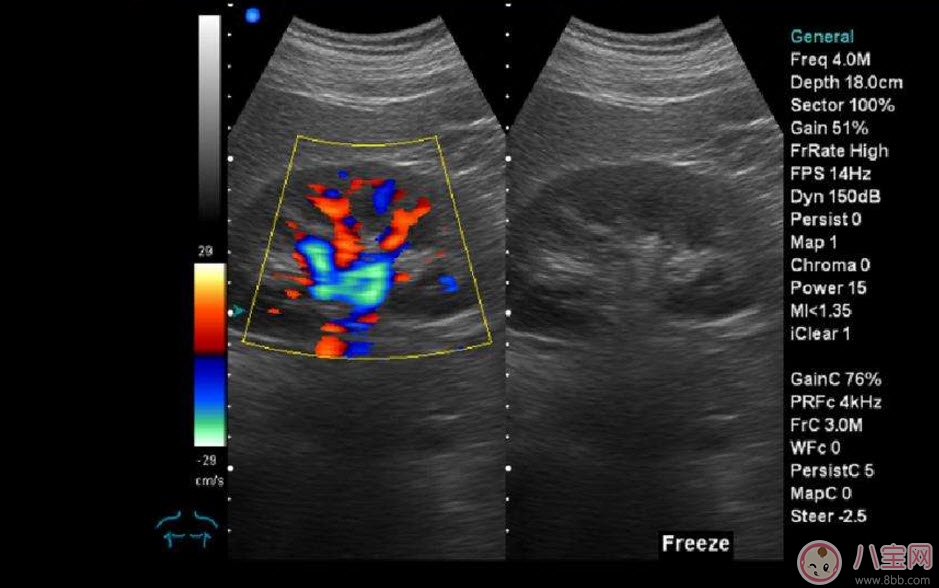

??B超也稱為二維超聲,分為黑白的和彩色的兩種。 彩超其實(shí)還是黑白的,彩超簡(jiǎn)單的說就是高清晰度的黑白B超再加上彩色多普勒,既具有二維超聲結(jié)構(gòu)圖像的優(yōu)點(diǎn),又提供了血流動(dòng)力學(xué)的豐富信息。彩超的分辨率會(huì)比一般黑白B超高一些,所以在需要做比較細(xì)致的檢查的時(shí)候,更多的醫(yī)生愿意通過彩超來檢查。例如,因?yàn)椴食苡貌噬珮?biāo)注血流,所以當(dāng)臍帶繞頸的時(shí)候就會(huì)看見寶寶的脖子上呈U形或者W形的血流,對(duì)是否臍帶繞頸也就一目了然了。目前用于產(chǎn)檢的超聲波一般都是二維的。

除了能觀察到通過B超觀察到的一切外,彩超能夠直觀成像,顯示更清晰,結(jié)果也更快速,可發(fā)現(xiàn)異常血流,為診斷胎兒先天性心臟缺陷提供了診斷依據(jù)。價(jià)格要比B超貴,大概在150元左右(會(huì)根據(jù)各地具體情況的不同而上下浮動(dòng))。二維彩超適用于整個(gè)孕期,特別是臨產(chǎn)前。二維彩超的圖像也并非就是彩色的,而是用彩色標(biāo)注心臟、血流等指標(biāo),其實(shí)就是高清晰度的黑白B超再加上彩色多普勒。觀測(cè)到的圖像以紅藍(lán)兩色血流方向?yàn)橹鳎嫦蛱筋^的呈現(xiàn)紅色,反之為藍(lán)色。這種技術(shù)能夠觀測(cè)到胎兒的血液流動(dòng)情況,有利于及時(shí)發(fā)現(xiàn)胎兒的異常。比如,發(fā)現(xiàn)胎兒頸部有血流環(huán),則意味著發(fā)生了可導(dǎo)致窒息死亡的臍帶繞頸。